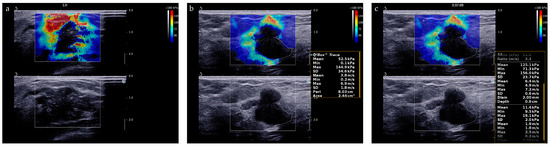

2.2. Ultrasound Image Acquisition

2.3. Ultrasound Image Evaluation

Appendix A. Detailed Descriptions of Shear Wave Elastography Parameters